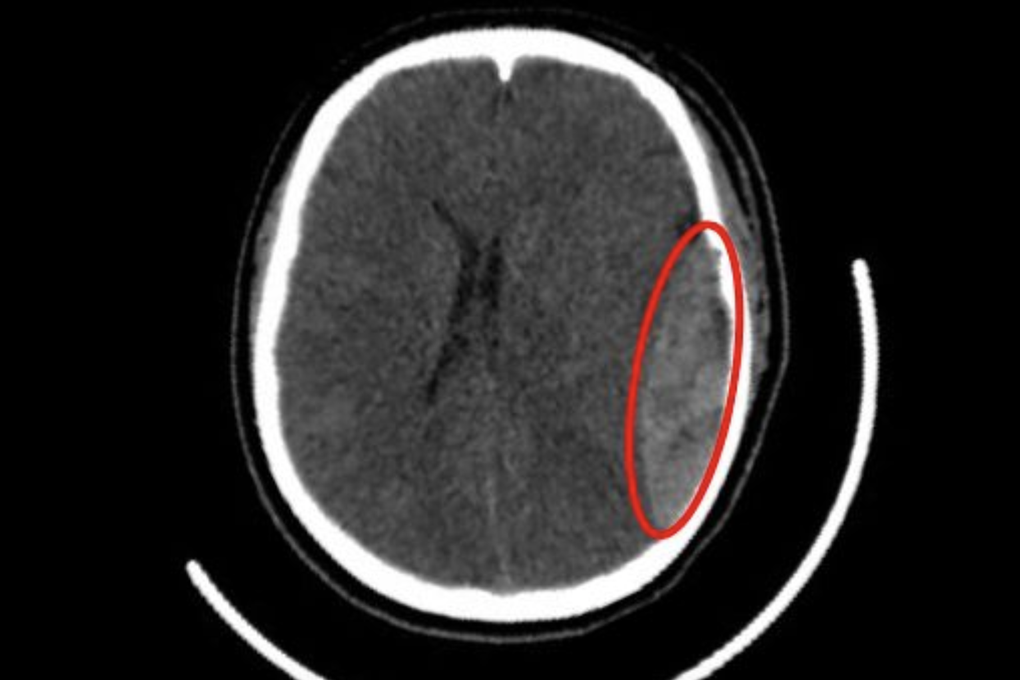

Kết quả chụp CT sọ não cho thấy, bệnh nhân có một khối máu tụ ngoài màng cứng, kèm theo nứt xương sọ vùng thái dương trái và có xu hướng chảy máu thêm.

Kết quả chụp CT sọ não ghi nhận bệnh nhân có một khối máu tụ (Ảnh: BV).

Đánh giá ban đầu cho thấy, nguồn chảy máu xuất phát từ việc nứt sọ thái dương và đứt động mạch màng não giữa. Trước tình hình này, người bệnh được chỉ định phẫu thuật cấp cứu, để lấy máu tụ ngoài màng cứng và cầm máu.